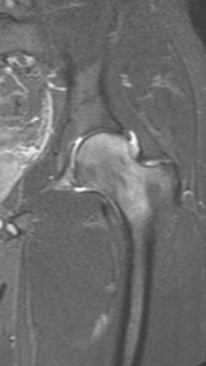

Асептический некроз тазобедренного сустава

3 процедуры ФДТ, 9 процедур MBST, 20 процедур ИПМТ